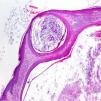

HistopathologySkin biopsy revealed the presence of keratin-filled cysts in the middle and upper dermis (Fig. 3).

Hair is present at birth and irreversible alopecia begins in the first months of life. Follicular papules develop on the scalp, face, and extremities in the first few years. In some cases, whitish patches also develop on the scalp. Biopsy reveals an absence of hair follicles and the presence of keratin-filled cysts in the dermis.4,6